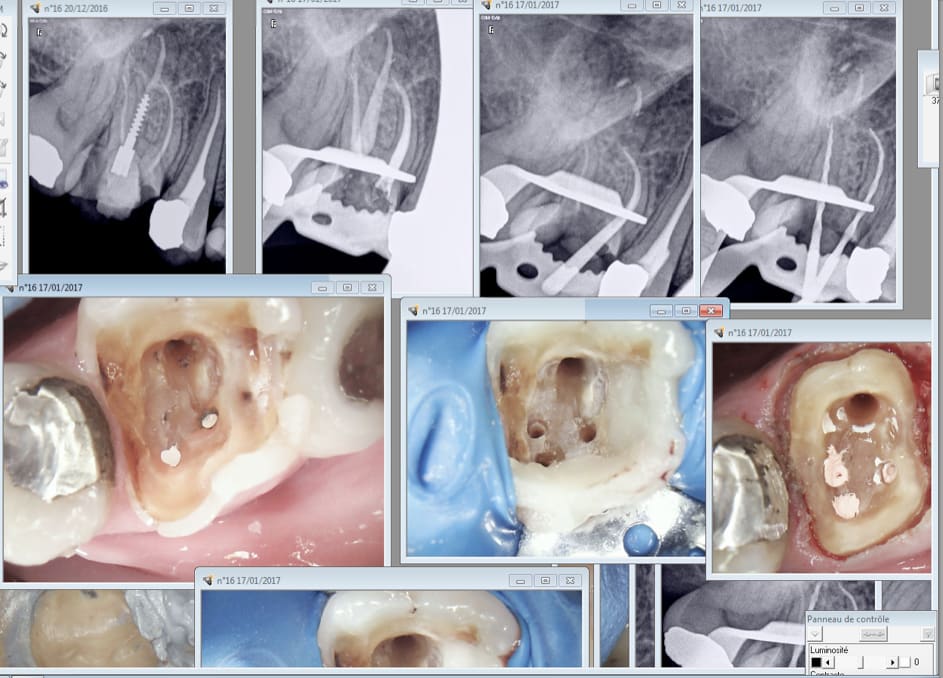

Les RTE notamment. Au fait il y a combien de canaux sur une molaire supérieure ? -)))